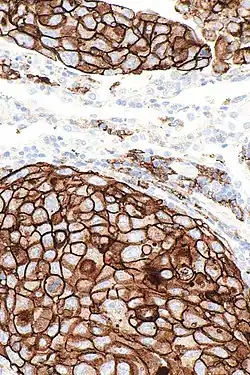

PD-L1 is shown to be highly expressed in a variety of malignancies, particularly lung cancer. In order to anticipate the effectiveness of gene therapy or systemic immunotherapy in blocking the PD-1 and PD-L1 checkpoints, PD-L1 might be employed as a prognostic marker and a target for anti-cancer immunity.[28] i.e. upregulation of PD-L1 may allow cancers to evade the host immune system. For example, an analysis of 196 tumor specimens from patients with renal cell carcinoma found that high tumor expression of PD-L1 was associated with increased tumor aggressiveness and a 4.5-fold increased risk of death.[29] In a model of A20 leukemia cells injected into F1 mice, NK cells killed target tumor cells with similar efficiency regardless of PD-L1 expression, whereas PD-L1 expression on A20 tumor cells conferred significant tumor protection against rejection by CD8 T cells confirming the role of the co-inhibitory receptor PD-1 in the modulation of their cytotoxic activity.[30]

Many PD-L1 inhibitors are in development as immuno-oncology therapies and are showing good results in clinical trials.[31] Clinically available examples include durvalumab, atezolizumab and avelumab.[32] In normal tissue, feedback between transcription factors like STAT3 and NF-κB restricts the immune response to protect host tissue and limit inflammation. In cancer, loss of feedback restriction between transcription factors can lead to increased local PD-L1 expression, which could limit the effectiveness of systemic treatment with agents targeting PD-L1.[33] CAR-T[34] and NK cells[35] targeting PD-L1 are being evaluated for treating cancer. pSTAT-1 and PDL-1 expressions also strongly correlate in prostate cancer.[36]

Upregulation of PD-L1 on immune cells (especially myeloid cells and macrophages) can also lead to formation of an immunosuppressive environment in a highly localized manner that also allow the cancer cells to proliferate or cause direct deletion of anticancer CD8+ T cells.[37][23]

PD-L1 analysis in TNBC is essential for selecting patients eligible for immunotherapy. Inter-observer and intra-observer agreement among the pathologists were found to be substantial. Cases around the 1% cut-off value are specifically challenging.[38]